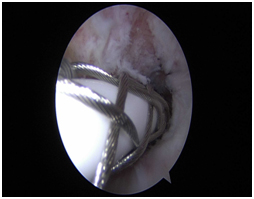

Arthroscopic photos from the surgery show removal of the os. The spinal needle is used to localize the os and demonstrate that it is loose. It is then removed arthroscopically with a burr. Care is taken to not disrupt the dorsal capsule.

Post Operative X-ray.

The patient has returned to competitive power lifting and remains symptom free.